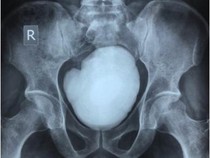

Penampakan Batu Kandung Kemih Seberat 900 gram, Ketahuan usai Ngeluh Pipis Berdarah Kamis, 19 Jun 2025 11:30 WIB